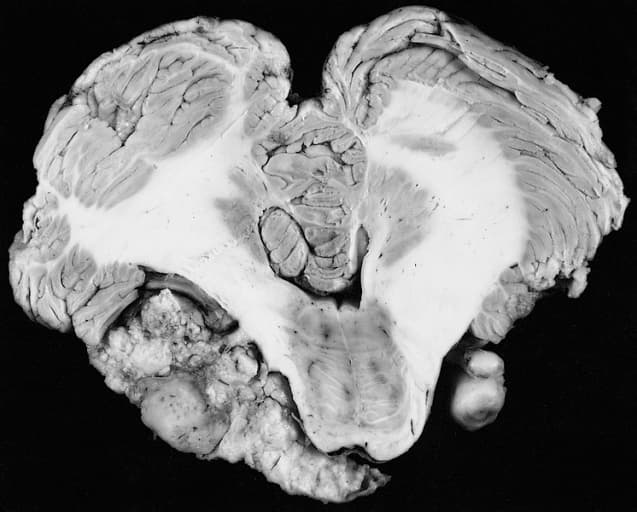

Le neurinome du nerf vestibulocochléaire ( paire crânienne) est une tumeur bénigne dont les signes cliniques sont variables et trompeurs : surdité de perception unilatérale, acouphènes, vertiges, paralysie faciale Il constitue un peu moins de 10 % des tumeurs intracrâniennes. L'incidence tend à croître mais probablement du fait d'un meilleur dépistage. L'âge moyen de la découverte est de 60 ans. L'usage intensif du téléphone portable a été suspecté un temps de favoriser la survenue d'un neurinome. Cette hypothèse a été infirmée. Par, contre, l'exposition au bruit pourrait avoir un rôle. Le neurinome de l'acoustique est le plus souvent isolé mais peut se voir dans le cadre d'une neurofibromatose de type II. Le neurinome est découvert lors d'un examen systématique (patient asymptomatique) dans un quart des cas. Le plus souvent on rencontrera un trouble de l'équilibre plus ou moins permanent à type d'embardée lors de la marche, augmentant aux mouvements brusques de la tête et à l'obscurité, associé à des signes auditifs unilatéraux qui sont prédominants, acouphènes anciens, hypoacousie avec mauvaise compréhension. On pourra également rencontrer une crise menièriforme de départ. On peut retrouver de manière inconstante un nystagmus spontané horizonto-rotatoire battant du côté sain, une surdité ou hypoacousie unilatérale. Il existe une aréflexie ou importante hyporéflexie unilatérale aux épreuves caloriques qui sont, la plupart du temps compensées, et même dans 10 % des cas la réflexie est normale. Il n'existe pas de signes de centralité à ce stade. Ce sont eux qui poussent le patient à consulter et sont quasiment constant lorsque le patient est symptomatique. Outre la surdité unilatérale, il existe une abolition ou une élévation du seuil du réflexe stapédien, une mauvaise compréhension vocale. Des acouphènes unilatéraux sont décrits dans plus de la moitié des cas. Les potentiels évoqués auditifs montrent un intervalle I/V allongé ou un tracé désorganisé. On confirmera le diagnostic par une cérébrale qui peut montrer des tumeurs de l'ordre de 2 mm de diamètre.